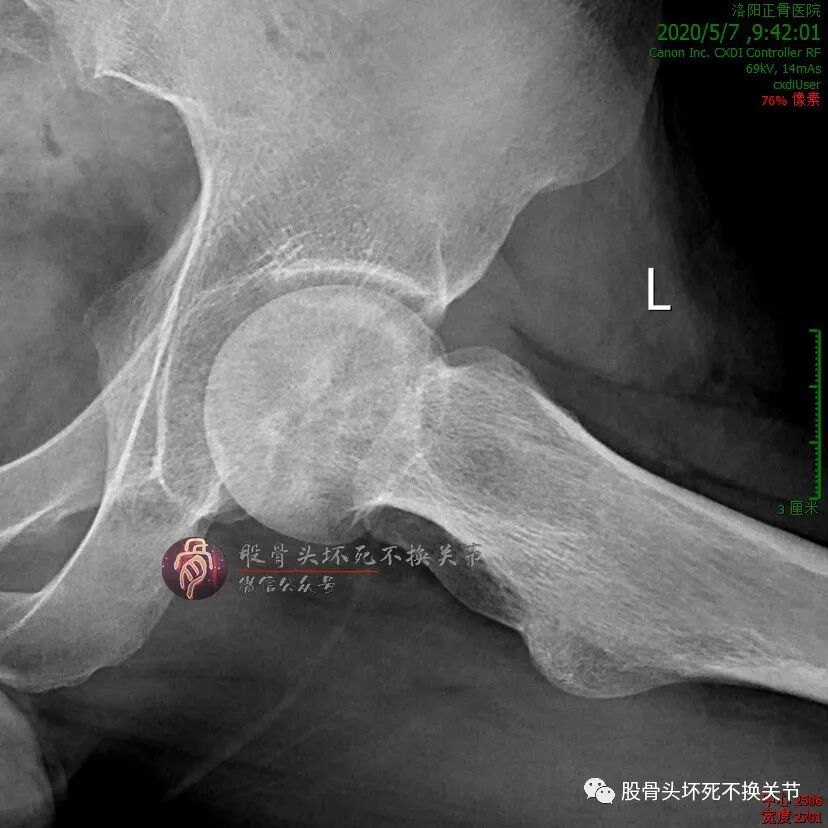

初次就诊2年后:

不错嘛,在工作、生活没耽误的前提下,病人偶尔来医院复查或治疗,也没有想象中的那么不便。初次就诊近3年复查:

这股骨头杠杠的!